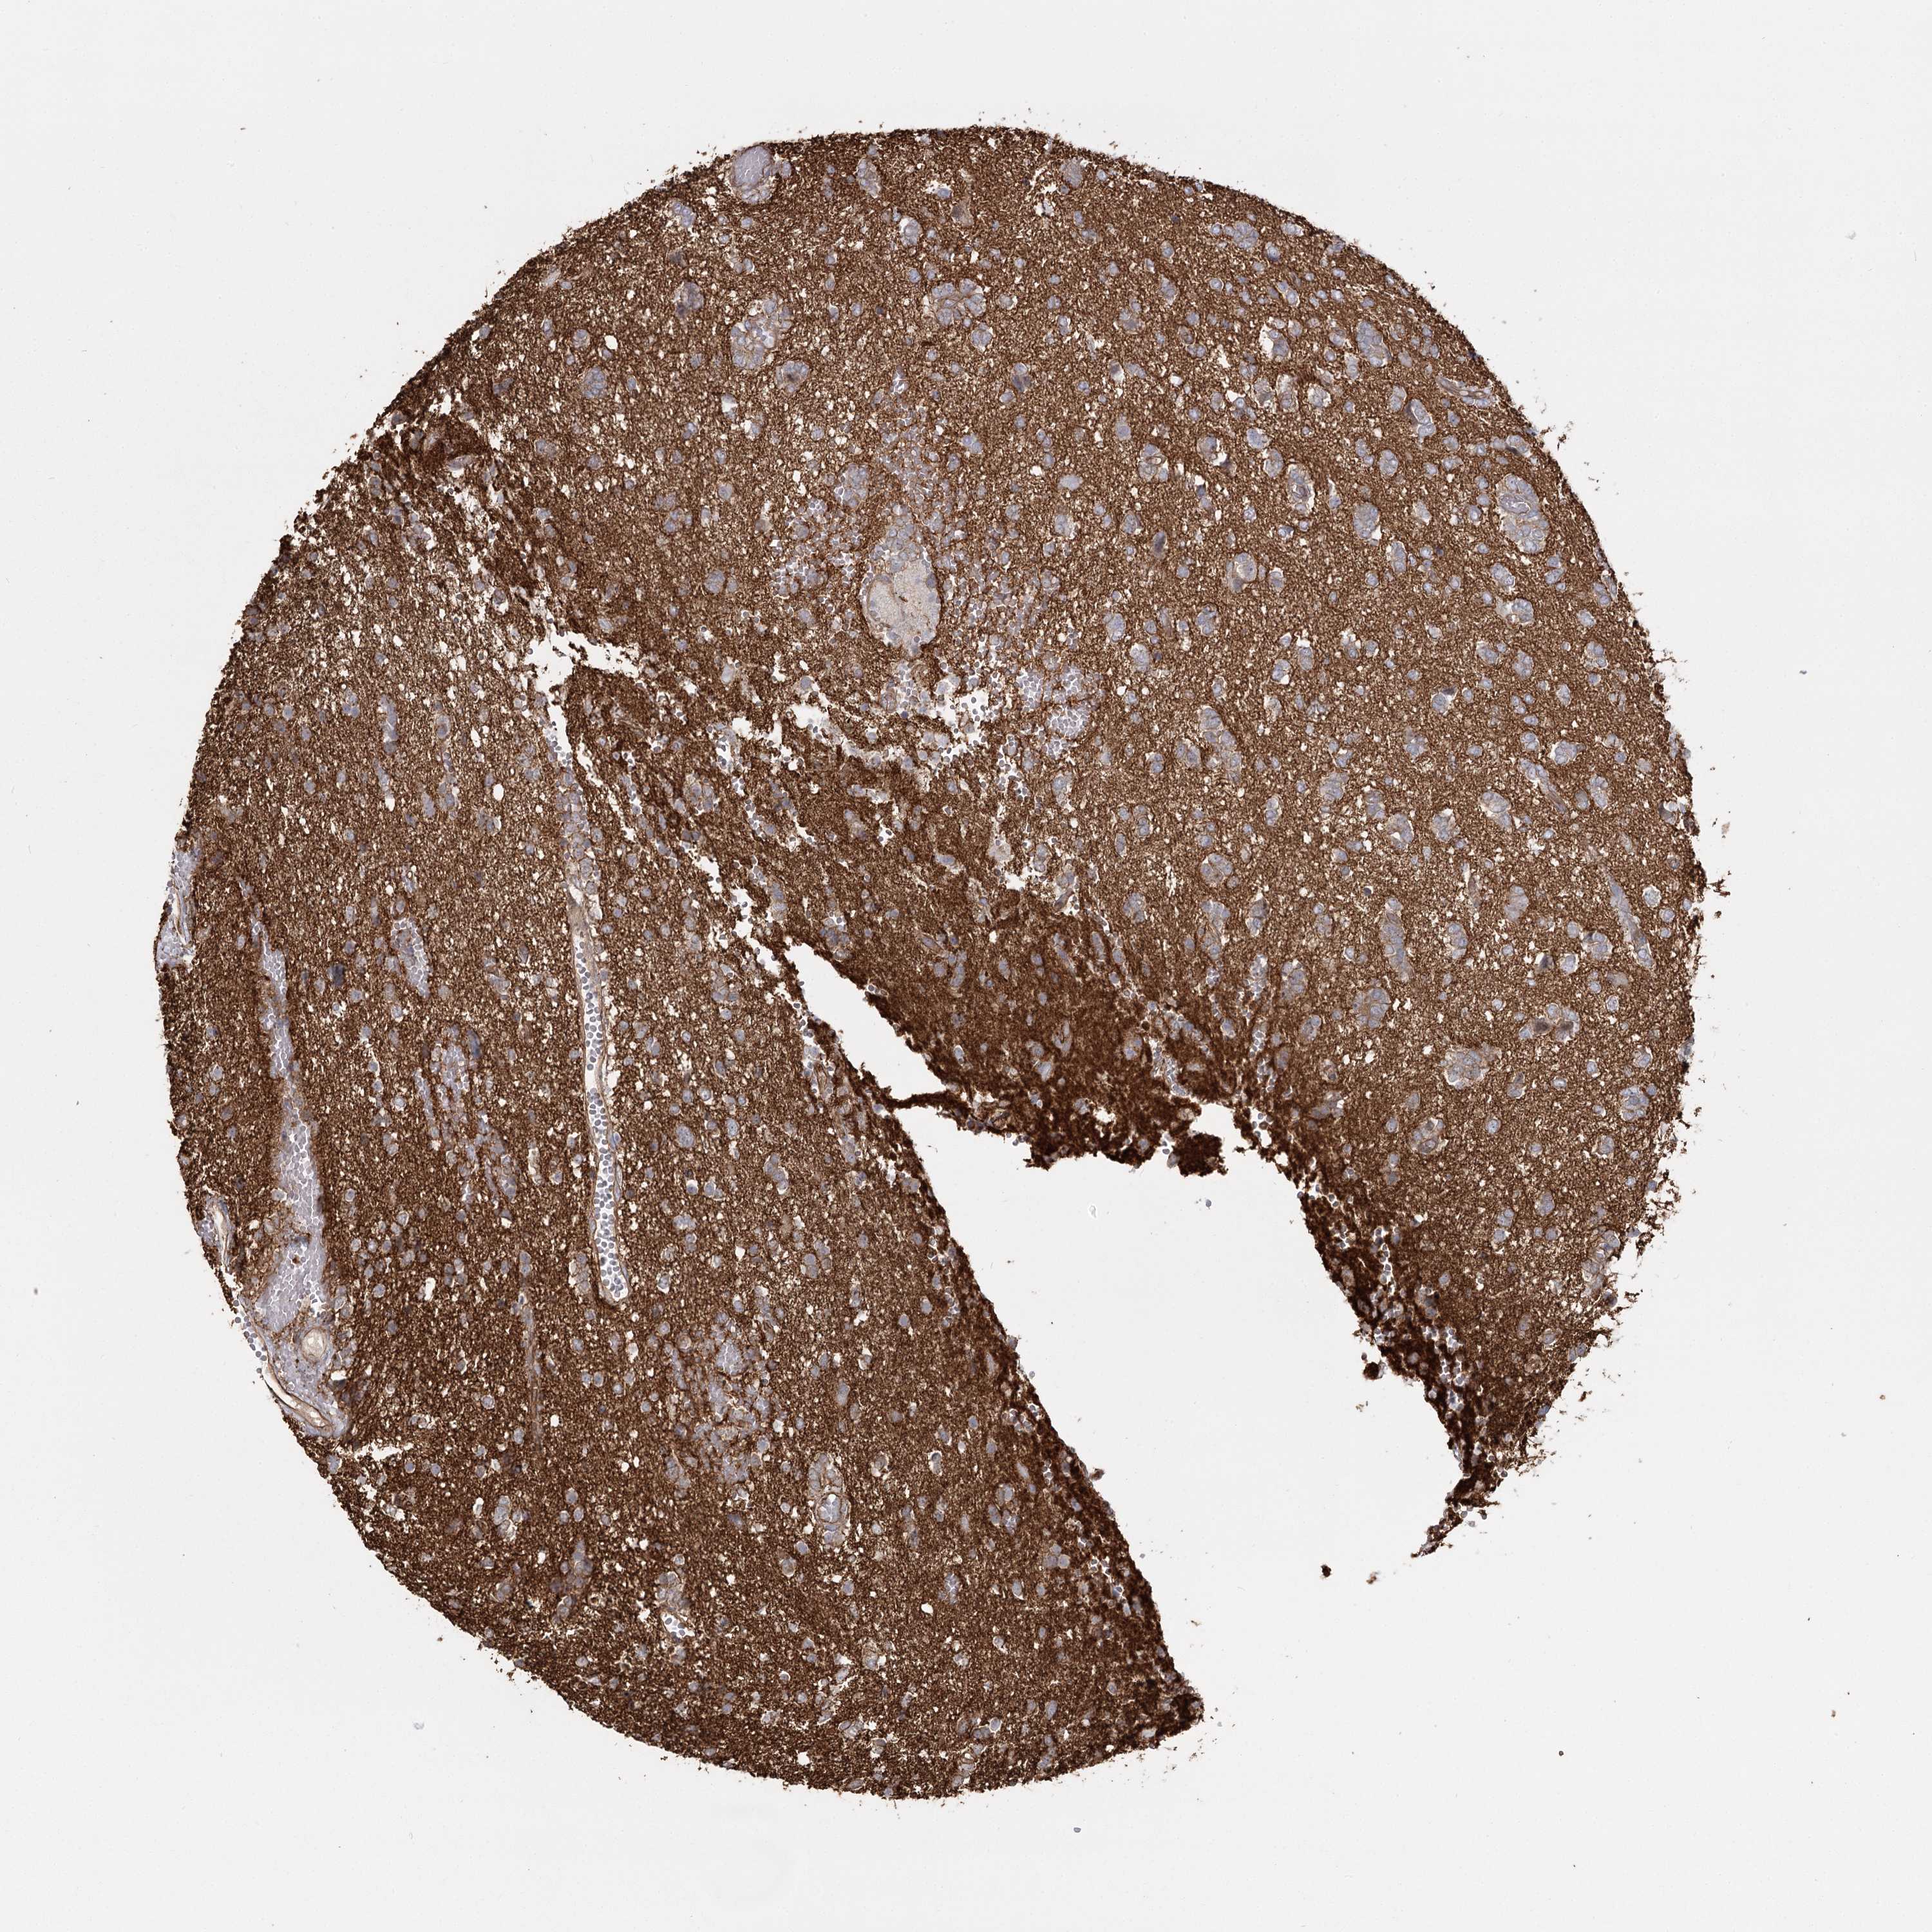

GLIOMA - Protein expressioni

A mouse-over function shows sample information and annotation data. Click on an image to view it in a full screen mode. Samples can be filtered based on level of antibody staining by selecting one or several of the following categories: high, medium, low and not detected. The assay and annotation is described here.

Note that samples used for immunohistochemistry by the Human Protein Atlas do not correspond to samples in the TCGA dataset.

Antibody stainingi

Antibody staining in the annotated cell types in the current human tissue is reported as not detected, low, medium, or high, based on conventional immunohistochemistry profiling in selected tissues. This score is based on the combination of the staining intensity and fraction of stained cells.

Each image is clickable and will lead to virtual microscopy that enables deeper exploration of all samples and also displays staining intensity scores, fraction scores and subcellular localization as well as patient and tissue information for each sample.

Antibody HPA036194

Staining

High

Medium

Low

Not detected

Intensity

Strong

Moderate

Weak

Negative

Quantity

>75%

75%-25%

<25%

None

Location

Nuclear

Cytoplasmic/membranous

Cytoplasmic/membranous,nuclear

Glioma, malignant, Low grade

Glioma, malignant, High grade

Glioblastoma, NOS